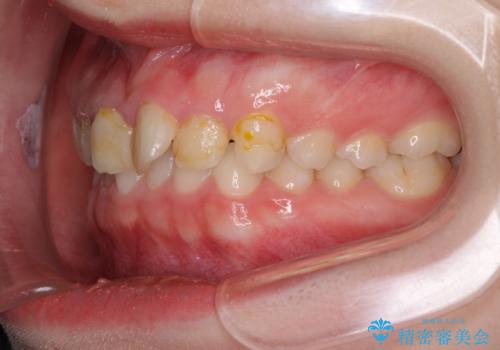

- 前歯の歯並びと虫歯を気にして来院された患者様です。

上下前歯の歯列不正はインビザラインにより歯列を整え、その後に、前歯5本をオールセラミッククラウンにて補綴治療することとしました。

矯正治療前に前歯のむし歯治療を行ったものの、樹脂で充填するには虫歯が広範囲であったため、審美的に問題がありました。

矯正治療にて歯並びを整えた後に、虫歯の大きかった5本の歯をセラミッククラウンにて補綴し、明るい口元になりました。